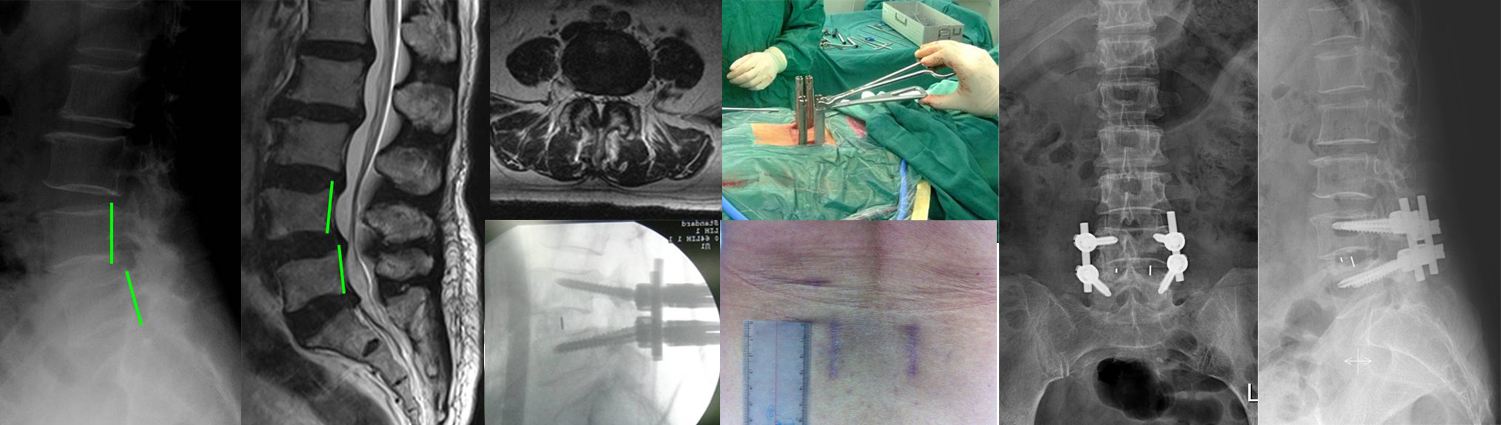

某女,腰疼5年,间歇性跛行,腰椎退变性侧弯兼腰椎管狭窄

某男,52 岁,L4,5骨折脱位5天,双下肢瘫,下肢有针刺觉,肌力0级2003.7.30行后路L4,5复位,L2-S1 USS固定,L3,4、L4,5间盘切除,植骨,L3-5减压

滑椎3度术后,腰痛伴间歇性跛行.外院内固定失败,滑椎未复位:后路减压滑椎复位椎弓根内固定,后路椎间cage植入

某女,55岁,后路椎板切除减压,间盘切除,L3-5内固定,后路椎间cage植入

某女,25岁,因腰痛入院.2002.5行后路峡部裂修补术,术后7月已愈合

某男,44岁,腰痛20年,加重2个月,查体:L5-S1间隙压痛,

诊断:L5-S1间盘源性下腰痛,2003.7.17行后路L5-S1间盘切

除,USS固定,Cage植入,植骨